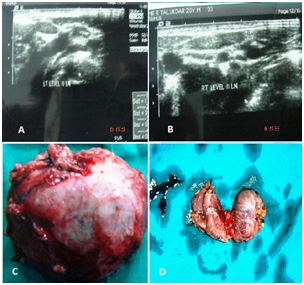

Fine needle aspiration of thyroid nodule was consistent with medullary thyroid carcinoma. Chromosomal study had shown point mutation in RET proto-oncogene. However none of his relatives or family members had such features. After careful evaluation and adequate control of hypertension, left sided radical adrenalectomy was performed. His intraoperative period was marked by considerable variations in his haemodynamic but postoperative period was uneventful. Three weeks later, total thyroidectomy (Figure 3) with modified bilateral neck dissection was performed together with parathyroidectomy and implantation of one of the parathyroid in the neck. Post operatively he developed tetany, which responded well to intravenous calcium supplementation.

Figure 3 A, B. USG showing enlarged level II neck glands on both side of neck. C. Excised specimen of left adrenal tumor. D. Total thyroidectomy specimen.

Figure 4 Histopathology of the adrenal tumor was consistent with pheochromocytoma while thyroid gland was detected to harbor bilateral multicentric medullary carcinoma with simultaneous independent foci of papillary microcarcinoma. Patient was put on oral thyroid hormone and calcium supplementation and a single antihypertensive drug. Patient was discharged at three weeks after thyroid surgery. He was initially followed at three monthly intervals for the first year and six monthly thereafter. The follow up protocol included careful physical examination and estimation of serum calcitonin, calcium, thyroid hormone and catecholamines along with ultrasonography of neck and abdomen. He is currently doing well. His only concern is the external appearance.